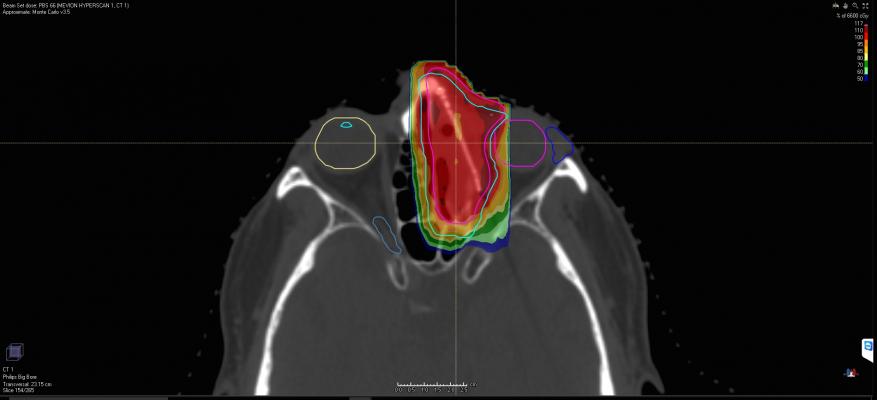

The Mevion S250i system is a compact proton therapy system capable of delivering conformal radiation therapy treatments using Hyperscan pencil beam scanning technology. The design of Hyperscan PBS technology overcomes clinical challenges that were previously faced by first-generation PBS systems.

Pencil beam scanning systems shape the delivered radiation dose by “painting” tumors spot-by-spot and layer-by-layer with sub-atomic particles. Prior to Hyperscan PBS, scanning proton systems struggled with delivery speed, according to Mevion. Long delivery times can undermine the high precision of the treatment due to the target tumor shifting under normal organ motion such as breathing.

Hyperscan PBS uses a compact beam delivery path reducing delivery times to less than 5 seconds for some fields. This “hyper-fast” treatment delivery reduces treatment errors due to the sensitivity to motion that current PBS technologies face when treating tumors affected by organ motion.

In addition, Hyperscan PBS utilizes the Adaptive Aperture proton multi-leaf collimator (pMLC). This technology uses a robotically controlled collimation system, capable of trimming the edges of the beam at every layer of delivery. This capability delivers up to a three times sharper drop off in radiation at the delivery field edge. This improves sparing of healthy tissue and limits unnecessary radiation to sensitive locations.